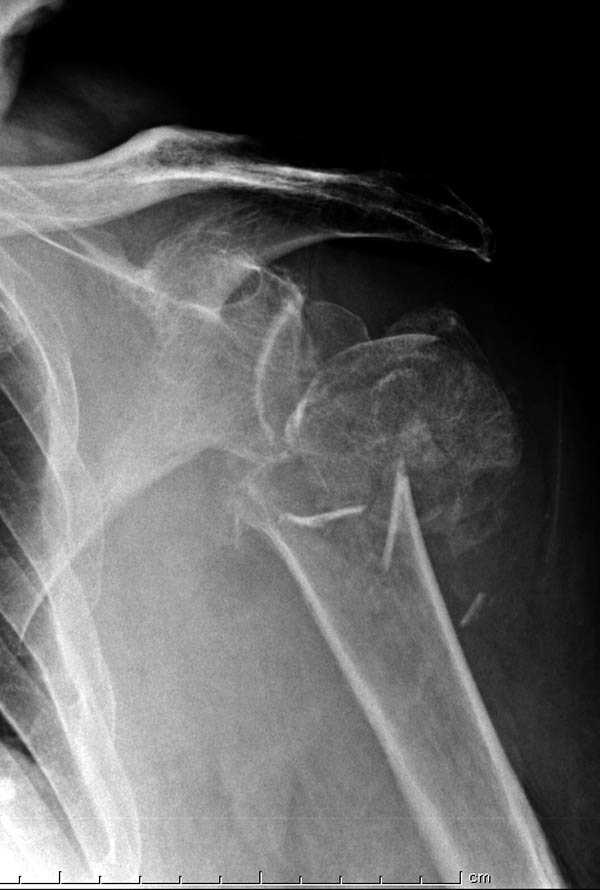

Пациентка Б.1953 г.р., врач-терапевт. Травма 27.11.08г. Падение с высоты роста. Выявлен закрытый не осложненный оскольчатый перелом хирургической шейки левого плеча со смещением. 02.12.08г. оперирована. Выполнена открытая репозиция и остеосинтез пластиной LCP Деост с дополнительной фиксацией отдельно лежащего фрагмента винтом. Послеоперационный период протекал без особенностей, заживление раны первичным натяжением. Швы сняты через 10 дней. Иммобилизация левой верхней конечности клиновидной подушкой 4 недели. По окончании срока – рентген-контроль и умеренная разработка плечевого сустава. В течении месяца функция левого плечевого сустава восстановилась удовлетворительно: поднятие руки до 110 гр., отведение - 90 гр. и до 110 гр. отведение с лопаткой. Отведение руки назад – 20 гр. Наружная и внутренняя ротация – 20 гр. Пациентка по настоянию самостоятельно вышла на работу. 27.03.09 при контрольном осмотре жалоб не предъявляет, болевой синдром в левом плечевом суставе отсутствует. Отведение плеча активно до 90 гр, пассивно с лопаткой до 110 гр., поднятие – 110 гр, отведение назад 20 гр, наружная и внутренняя ротация по 20 гр. На контрольных рентгенограммах отмечается смещение металлоконструкции, ротация головки плеча с приведением дистального отломка на 13 гр. и смещением к зади на 30 гр. Рентгенограммы прилагаются. Ваш взгляд на дальнейшую тактику лечения пациентки?

Ни какой миграции и смещения пластины нет, это изначальные смещения при остесинтезе.

Нет аксиальной проекции сразу после вмешательства. Возможно, никакого значительного смещения нет, все осталось так, как первично сопоставили...и,

Уважаемый Евгений, похоже, что первый и второй Р-снимки выполнены несколько в разных положениях(ротация) плечевой кости, в связи с этим создается впечатление смещения пластины. Остеосинтез выполнен при угловом смещении отломков.Таковым и остался. Данная ситуация была бы очевидна гораздо раньше, если бы при контрольной Р-графии были выполнены снимки в 2-х проекциях.(Не в обиду, сам иногда выполняю только один).

Здесь пример открытой репозиции 57 летнего с переломом плеча (1,2) смещение обнаружено на интероперационном снимке. При нормальной прямой проекция (3) угловое смещение обнаружили в аксиальной проекции (4)